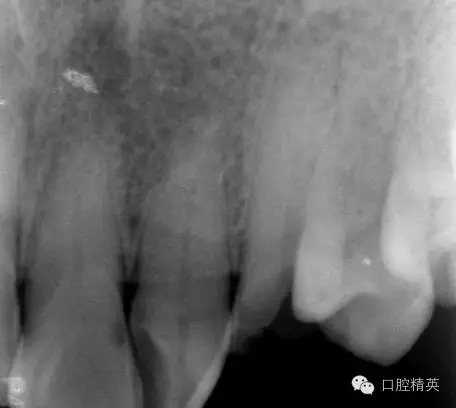

口內(nèi)檢查: 23殘根,位于齦上3MM,根管口探無反應(yīng),叩(+-),無松動,牙周無紅腫.X片示:23根管無阻射,根尖骨密度降低.

圖2 治療前X片: 23殘根,根尖區(qū)骨密度降低.